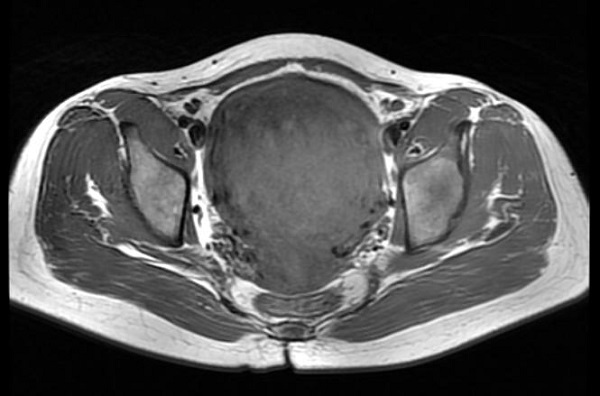

入院后给予抽血检查,随即检验科回报危急值:血红蛋白(46g/L)。立即给予输血治疗后,患者头晕、乏力等症状较前明显好转。完善盆腔磁共振,肌壁巨大子宫肌瘤(10.8cm×8.8cm×8.4cm)。经过制定详细手术计划后,排除手术禁忌,给予行“选择性子宫动脉栓塞术”。

(术前磁共振)